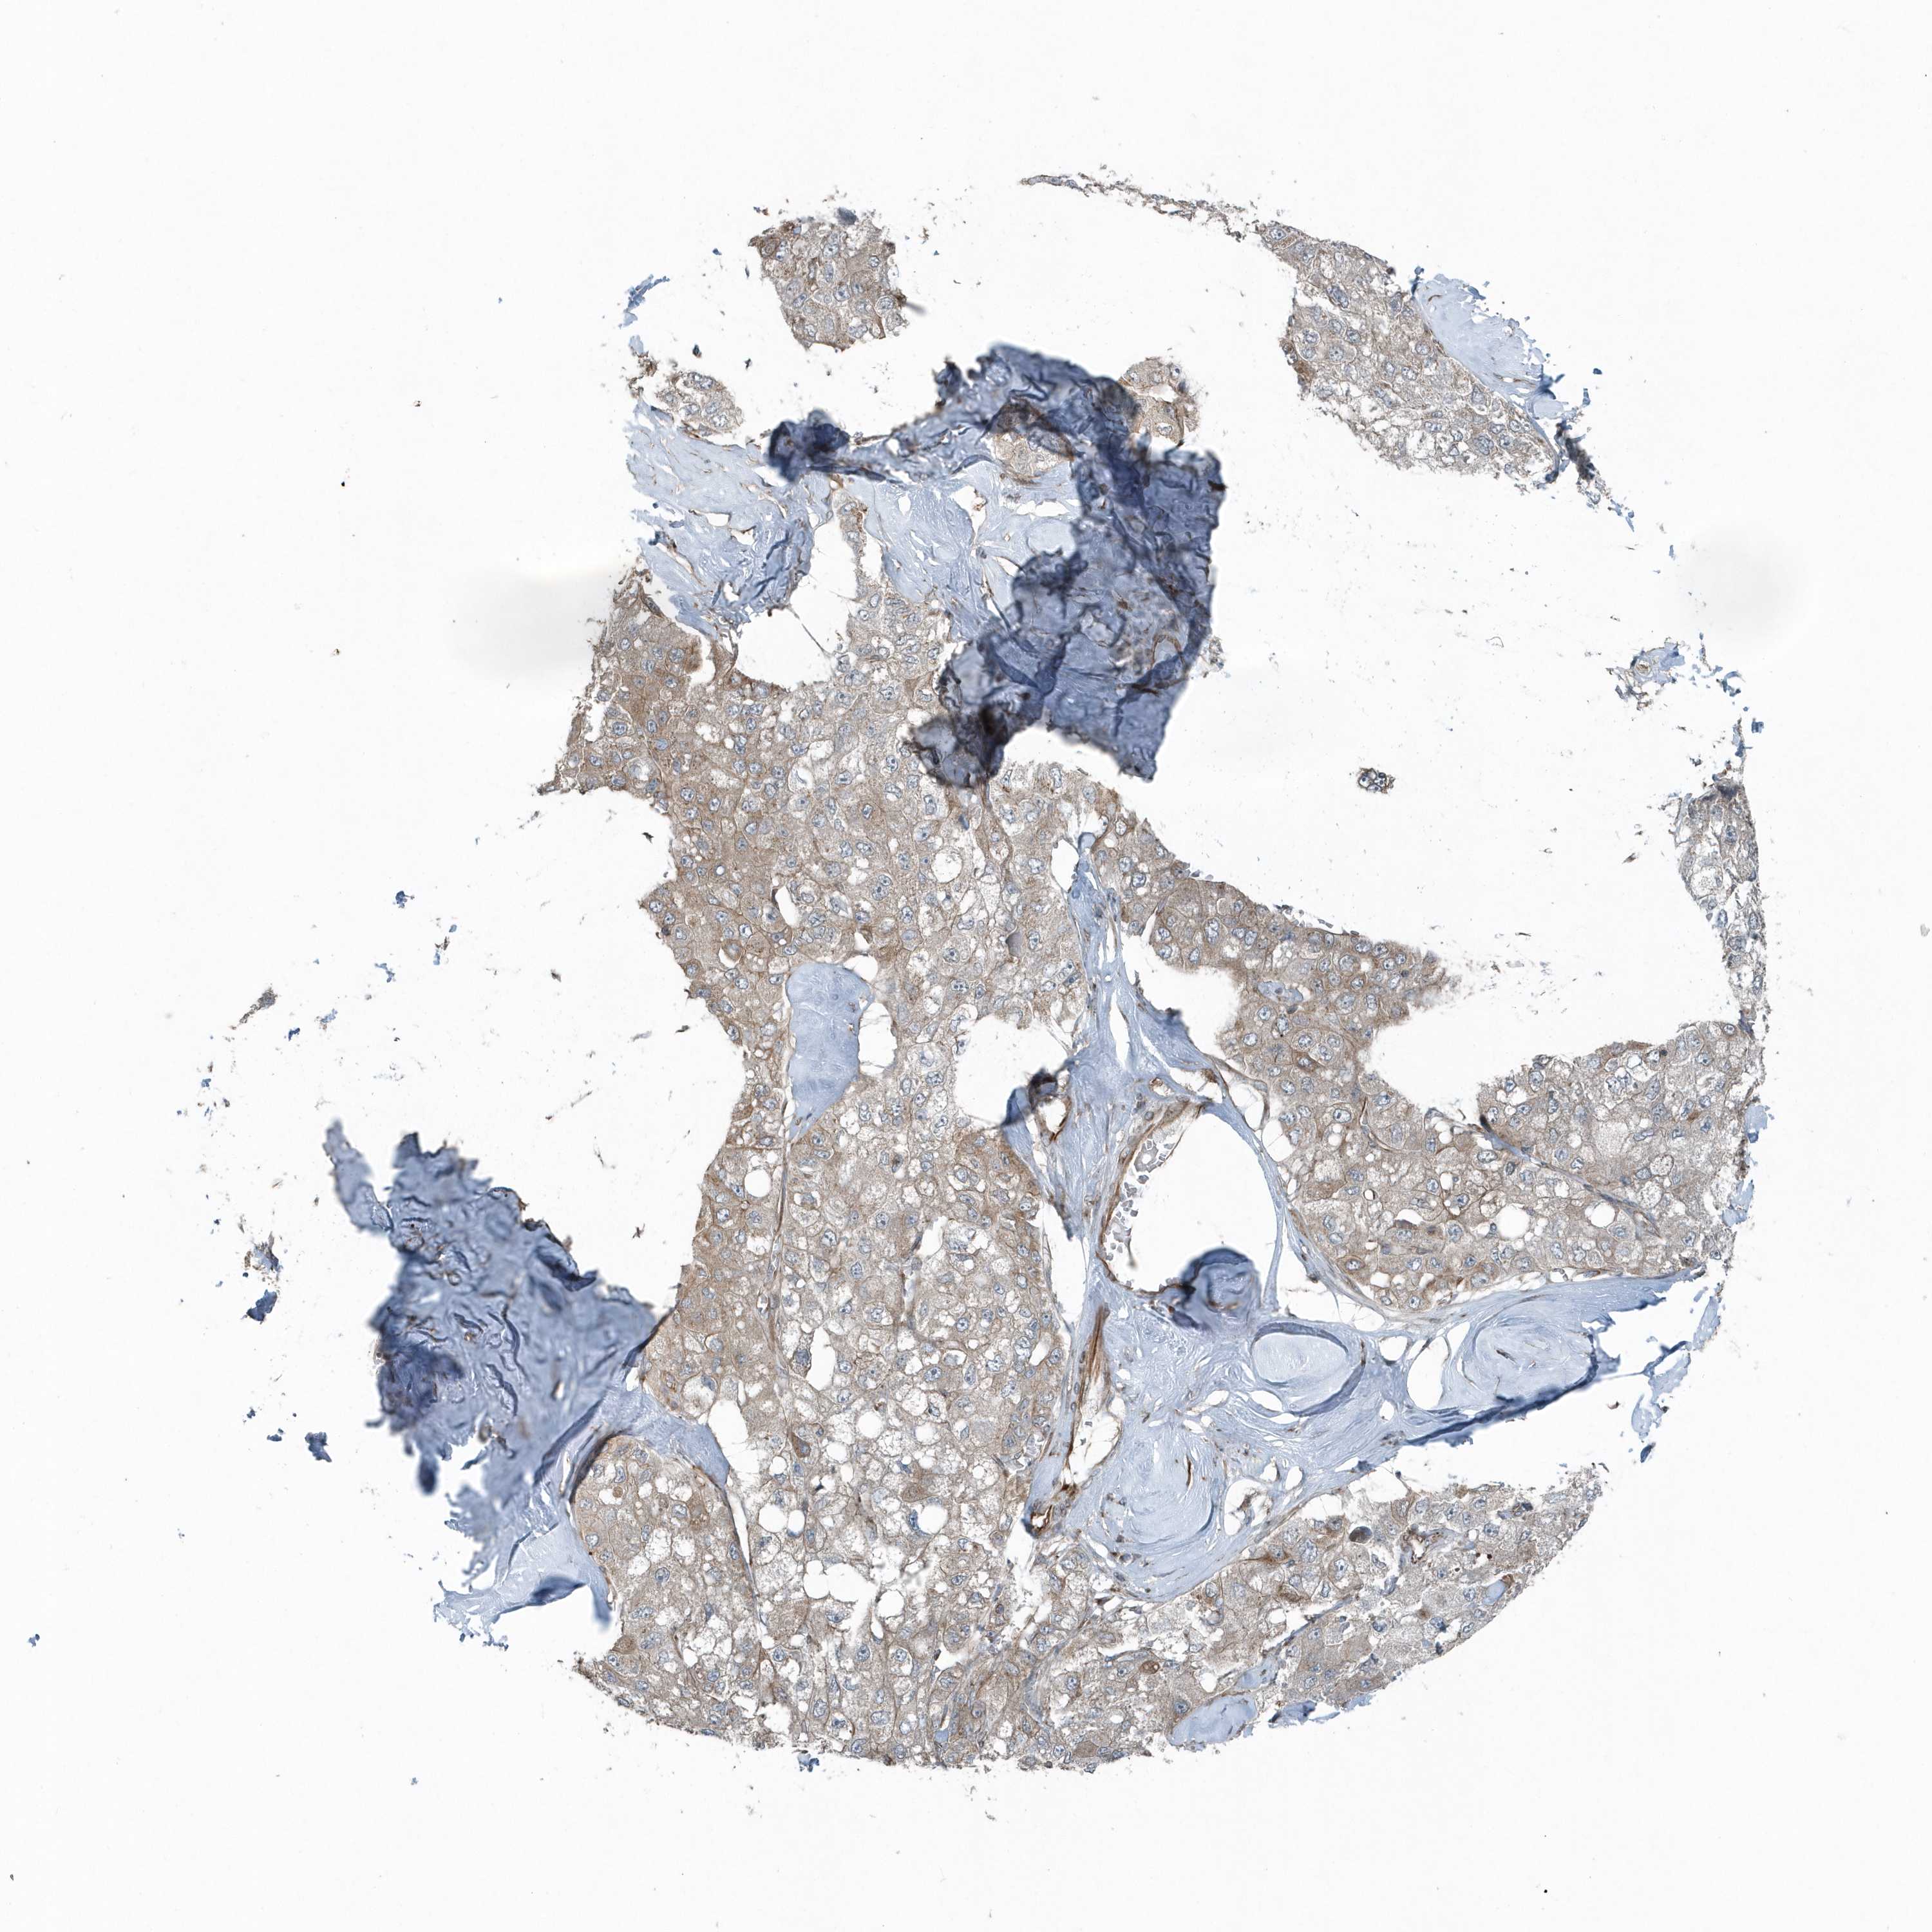

LIVER CANCER - Protein expressioni

A mouse-over function shows sample information and annotation data. Click on an image to view it in a full screen mode. Samples can be filtered based on level of antibody staining by selecting one or several of the following categories: high, medium, low and not detected. The assay and annotation is described here.

Antibody stainingi

Antibody staining in the annotated cell types in the current human tissue is reported as not detected, low, medium, or high, based on conventional immunohistochemistry profiling in selected tissues. This score is based on the combination of the staining intensity and fraction of stained cells.

Each image is clickable and will lead to virtual microscopy that enables deeper exploration of all samples and also displays staining intensity scores, fraction scores and subcellular localization as well as patient and tissue information for each sample.

Antibody HPA035849

Antibody HPA035850

Staining

High

Medium

Low

Not detected

Intensity

Strong

Moderate

Weak

Negative

Quantity

>75%

75%-25%

<25%

None

Location

Nuclear

Cytoplasmic/membranous

Cytoplasmic/membranous,nuclear

Cholangiocarcinoma

Carcinoma, Hepatocellular, NOS